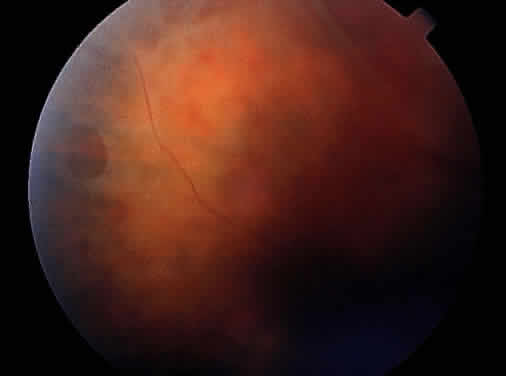

Peripheral retinal schisis is present in half of the patients and in 96% is located in the inferotemporal quadrant.48 At least initially, the inner layer of the schisis is attached to the vitreous and features vessels, internal limiting membrane, and nerve fiber layer. These tissues undergo progressive atrophy as well as reactive gliosis, which in a perivascular location may appear as vascular sheathing (Fig. 3). Total atrophy may result in dehiscences and peripheral arborization of the retinal vasculature.33,34,45 Optic atrophy may follow.40 The outer layer of the schisis cavity also undergoes atrophy, reactive gliosis, intralayer pigment migration, and hole formation. A rhegmatogenous detachment may be the sequela in 4% to 22% of all patients.30,42,49,51–53 With time, the vitreous undergoes syneresis and detachment.31,33,40 Vitreous detachment actually may improve the schisis by releasing traction. Adhesions to retinal vessels are responsible for frequently found vitreous hemorrhages.29,31,40